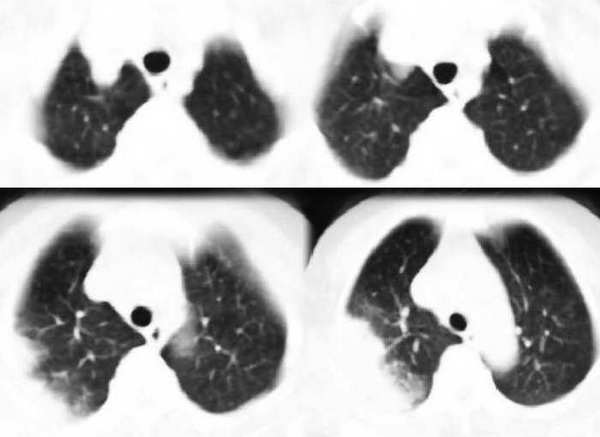

咳嗽10多天,畏寒,发热3天,

右肺大片状阴影,边缘模糊,其内见充气支气管征。肺门结构正常。支持肺炎性病变。

右肺大片渗出性实变,其内见支气管征,考虑肺炎

右肺上叶尖后段大片扇形实变影,密度较均匀,内见支气管空气造影征,气管腔静脉间淋巴结稍大呈小结节影,结合临床考虑大叶性肺炎。

右肺上叶尖后段大片扇形实变影,边缘略呈云片状渗出。并见“支气管气相”,结合病史支持大叶性肺炎诊断。建议正规抗炎复查。